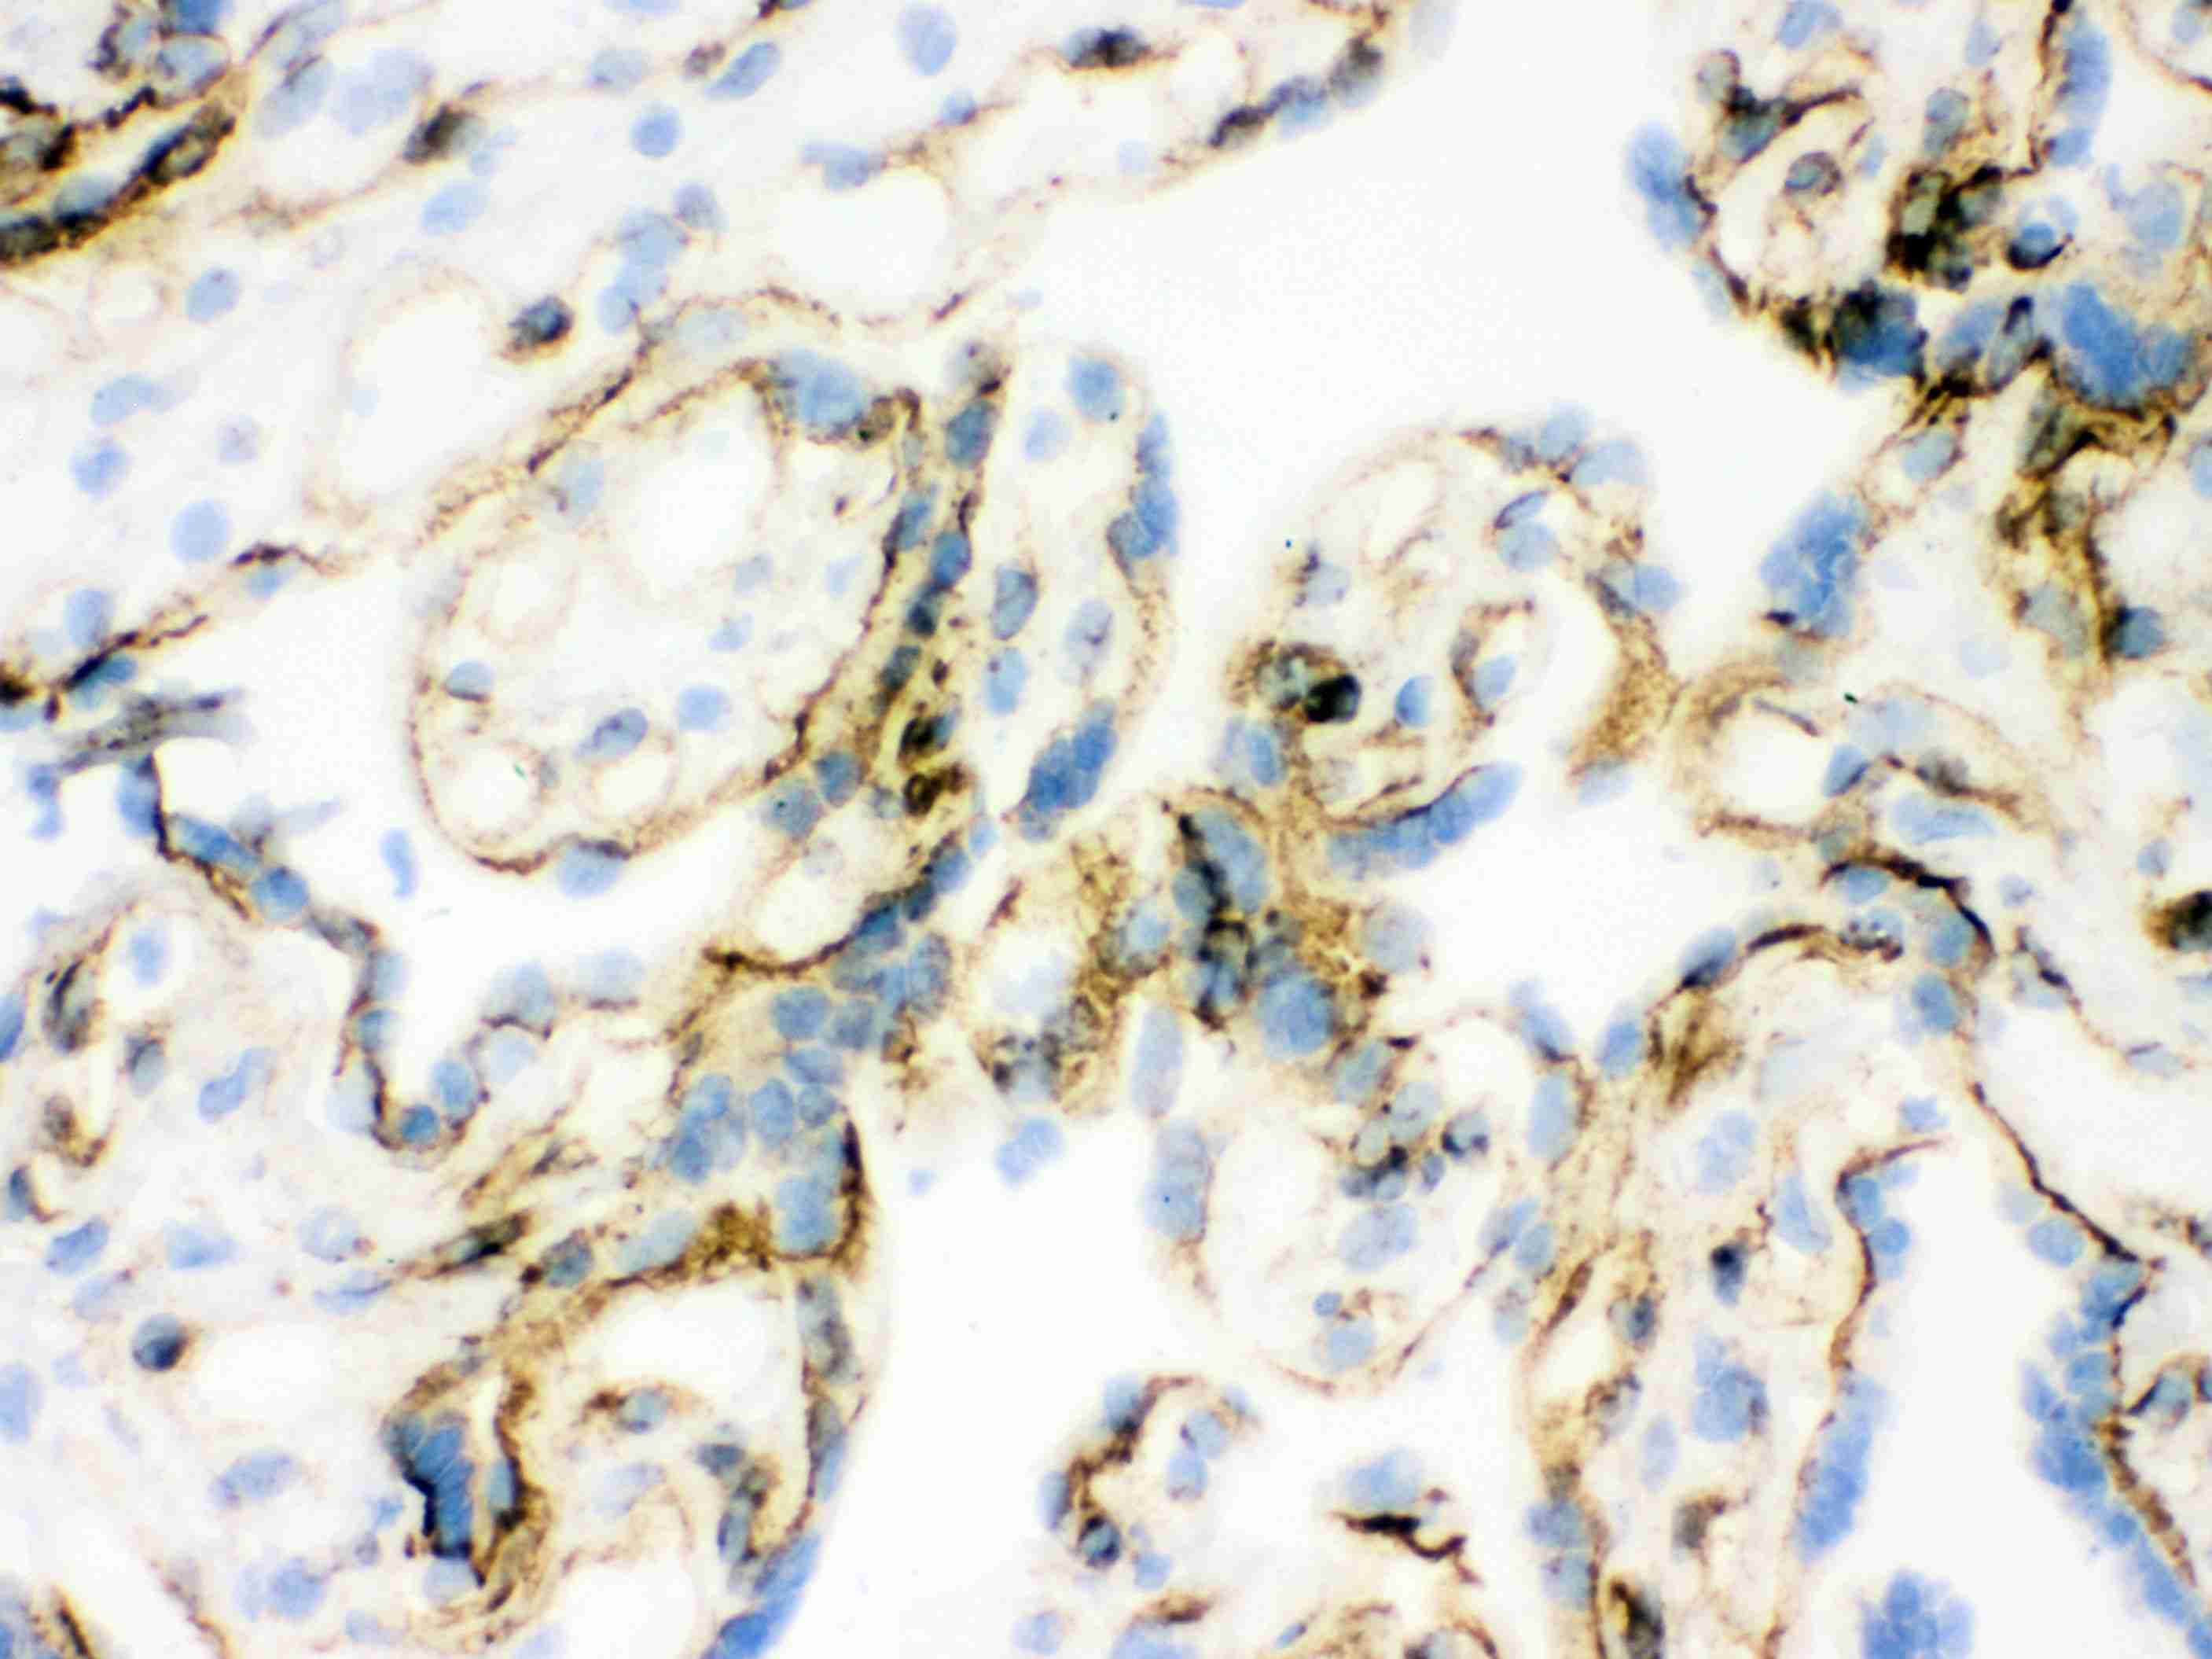

IHC analysis of Vinculin using anti-Vinculin antibody (BM1611).

Vinculin was detected in frozen section of human placenta tissues. The tissue section was blocked with 10% goat serum. The tissue section was then incubated with 1μg/ml rabbit anti-Vinculin Antibody (BM1611) overnight at 4°C. Biotinylated goat anti- mouse IgG was used as secondary antibody and incubated for 30 minutes at 37°C. The tissue section was developed using Strepavidin-Biotin-Complex (SABC)(Catalog # SA1021) with DAB as the chromogen.